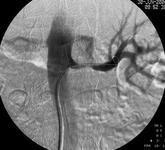

腎臟損傷約占所有泌尿生殖道損傷的65%左右。原因有鈍性損傷(80%),貫通傷(戰(zhàn)爭(zhēng)期間及高犯罪地區(qū)增加),以及醫(yī)源性損傷(由于手術(shù),體外震波碎石或腎活檢)。并發(fā)癥包括出血不止,尿外滲,膿腫形成和高血壓。

- 常見(jiàn)癥狀:尿外滲、紅細(xì)胞壓積偏高、血尿、低位腰痛、腎膿腫、高血壓